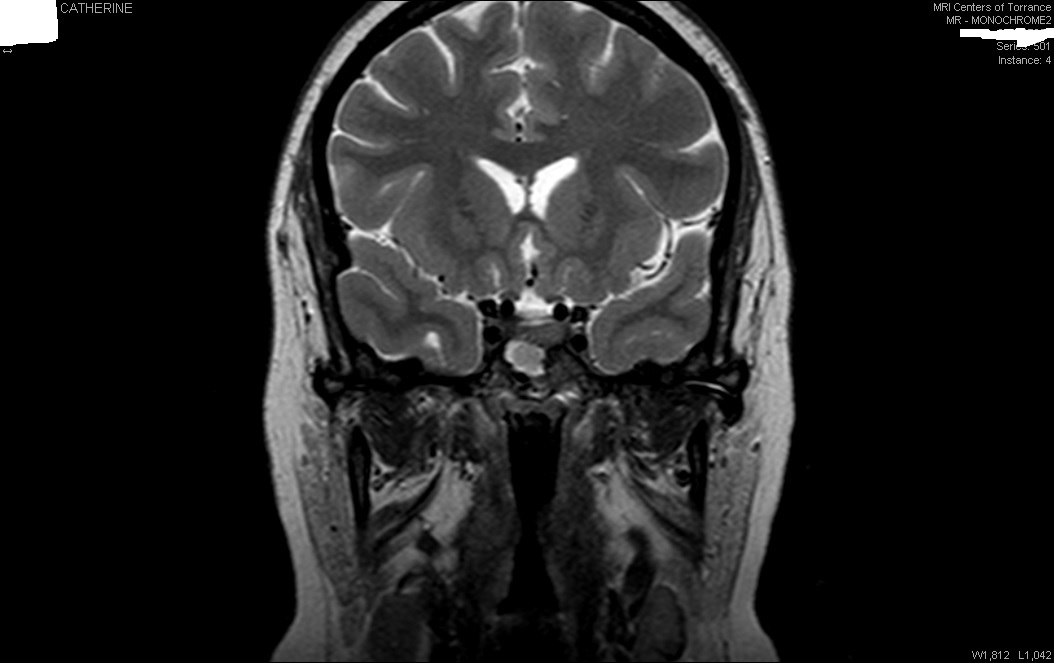

Here are the five pictures he sent back with his comments about them:

The arrows indicate the hypo enhancing spots on the dynamics (first two pictures).  The [third] picture is a spot that he said is “very concerning.”  Then there is a post-enhanced hypo-enhancing spot where it doesn’t belong (ie, there is an area that didn't absorb the dye like it should, which is common with these type of tumors).  The side view shows what could be tumor, but it could also be a juncture spot.

I made the pictures with arrows larger since they turned out pretty small on here, so it is hard to see.  To start, look right under the center of the brain for the white blob (from the side) or arch(from the back) that is the pituitary, surrounded by black arteries, etc.  That little blob/arch is where you'll find the arrows.